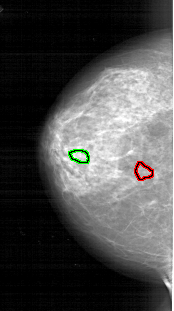

FILE: A_1744_1.LEFT_MLO.OVERLAY

TOTAL_ABNORMALITIES 1

ABNORMALITY 1

LESION_TYPE CALCIFICATION TYPE PLEOMORPHIC DISTRIBUTION CLUSTERED

ASSESSMENT 4

SUBTLETY 2

PATHOLOGY BENIGN

TOTAL_OUTLINES 1

FILE: A_1744_1.LEFT_CC.OVERLAY

ABNORMALITY 2